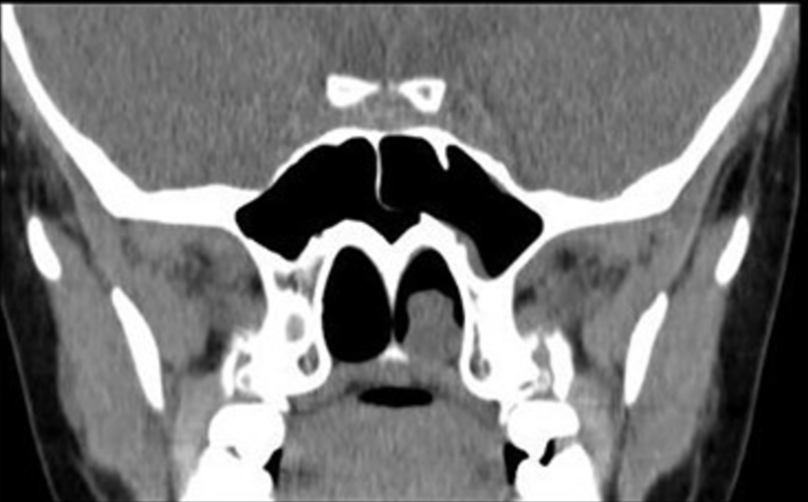

前鼻镜检查显示下鼻甲肥大,粘膜过敏,分泌物增多,未见新生物。鼻内无持续性脓性鼻漏。在咽喉检查中,见一个巨大的红色草莓状肿物在口咽部向后脱垂。对左鼻孔进行了鼻内窥镜检查 (FNE),显示从中鼻道延伸到后鼻孔的息肉和清晰的右气道。进行了计算机断层扫描 (CT) 扫描(图1和图2)显示从左中鼻道产生的软组织肿物,向后延伸并到达左侧后鼻孔(图 2)。

图1

鼻内镜检查和 CT 扫描放射学评估是诊断 ACP 的金标准。鼻内窥镜检查显示 ACP 为从中鼻道出现的平滑息肉状肿块,延伸至后鼻孔和鼻咽。CT 扫描的主要发现是软组织肿块,不会侵蚀相邻的骨结构。CT 扫描也用于 ACP 的分期分类。磁共振成像可用于辅助诊断并排除血管瘤性息肉。